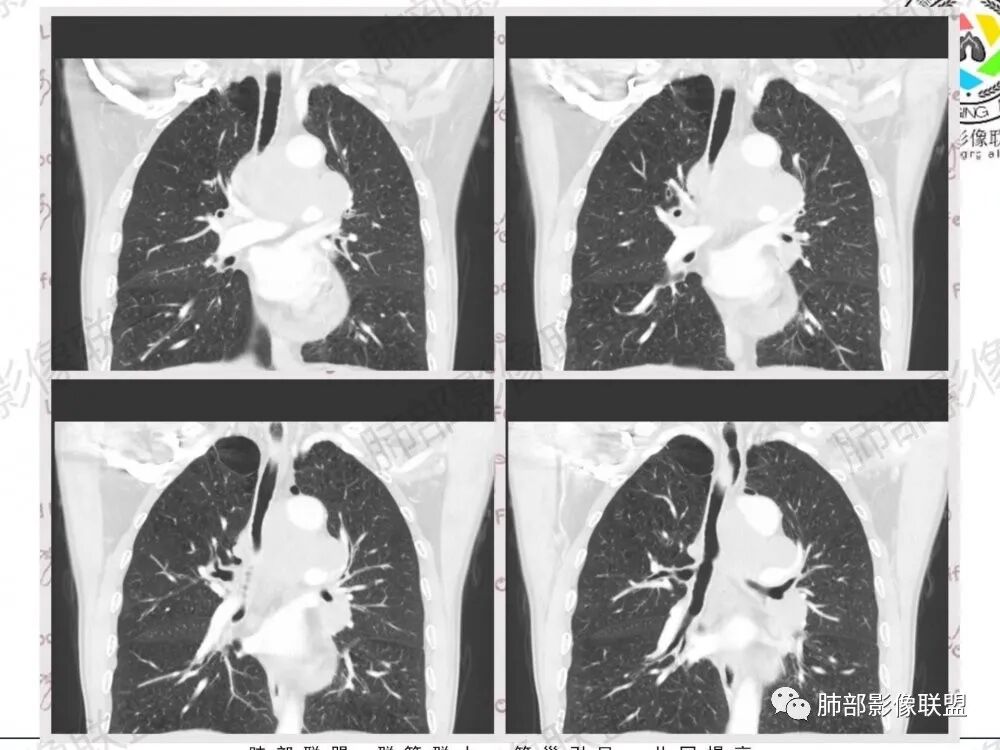

57岁男性,长期吸烟史,有血吸虫病史,有粉尘接触史。发现纵隔淋巴结肿大2年,声嘶伴咳嗽咳痰半月。两年前胸部CT见左上肺尖后段结节并肺门淋巴结肿大,治疗后左上肺结节消失。目前胸部CT:肺气肿,左上肺尖后段见条索影(原来结节治疗后的改变?),肺门、纵隔淋巴结肿大并融合,似见薄壁包膜样强化。考虑淋巴结结核可能性大,注意鉴别淋巴瘤、转移、结节病等。

左上肺门和左下肺门淋巴结,纵膈淋巴结肿大,融合明显。右肺门未见肿大淋巴结。上腔和邻近左上,下肺动脉推移受侵变细明显。先考虑恶性肿瘤的淋巴结转移。病理亚型不敢定了,前两天刚碰见一个这样的腺,先猜小细胞。既往结核粉尘吸入,淋巴瘤第二位吧。

中老年男性,长期吸烟,肺气肿明显,发现纵隔淋巴结两年了,声音嘶哑,病灶压迫喉返神经了?喉部有占位吗?左肺尖小片状病灶,周围多发长条纤维牵拉,胸膜增厚,纵隔及左肺门多发肿大淋巴结,增强后显示淋巴结融合且坏死明显,薄环状强化。如果是恶性肿瘤,小细胞癌或者鳞癌,肺内病变应该增大增多了;一元化我考虑纵隔淋巴结结核,左肺尖结核灶。

南边:纵隔淋巴结肿大病史2年,右上肺结节消失,这个病史值得玩味淋巴结肿大,中纵隔

左肺门,后纵隔

肺内好像就是慢阻肺痰栓

淋巴结有融合

影像特点:

1.左肺门及纵隔见异常增大淋巴结,部分融合,不均匀轻度强化,未见明显坏死。

肿大淋巴结与纵隔血管等结构“无缝”贴合。

2.纵隔增宽但依旧居中。

别忘了,患者左肺上叶那个略显饱满的的小结节,有理由相信那是发源地。

因为这些符合肺癌的整个转移路径!